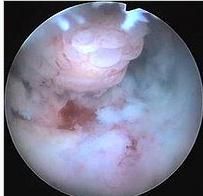

子宮內膜息肉子宮內膜息肉是由於宮內膜增生過盛構成,任何年齡均可發生,很常見的類型的局限性的內膜腫物,突出於子宮腔內、光滑、肉樣硬度,蒂長短不一,長者可突出於宮頸口外,有的蒂較短。凡借細長的蒂附著於子宮腔內壁的腫塊,臨床上都可稱為子宮息肉。因此,在宮腔內的息肉樣腫塊,可能是有蒂的黏膜下肌瘤、子宮內膜息肉、子宮腺肌瘤樣息肉和惡性息肉(癌或肉瘤)。較小的息肉一般無臨床症狀。有的露出宮頸外的息肉在房事後流血就診被發現。對蒂較長者可在宮腔鏡直視下用雷射手術切除,對同時發現的較小的息肉一併處理。子宮息肉是腔內鏡下雷射手術的最佳適應症。

大體觀察,最常見的類型是局限性的內膜腫物突出於子宮腔內,單個或多發,灰紅色,有光澤,一般體積較小,平均直徑在0.5~2cm之間。小的僅有1~2mm直徑,大而多發者可充滿宮腔。蒂粗細、長短不一,長者可突出於子宮頸口外。有的蒂較短,呈瀰漫型生長。息肉表面常有出血壞死,亦可合併感染,如蒂扭轉,則發生出血性梗死。

擴張宮頸,摘除息肉,繼之搔刮整個宮腔,可將瀰漫型小息肉刮除,並送病理檢查。術後應定期隨診,注意復發及惡變,及時進行處理。後來有人採用宮腔鏡下手術切除或雷射治療小型息肉,獲得成功。